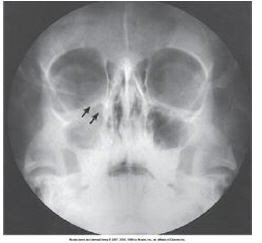

which paranasal sinuses are labeled with the letter A in this image

frontal

letter B

letter C

maxillary sinuses